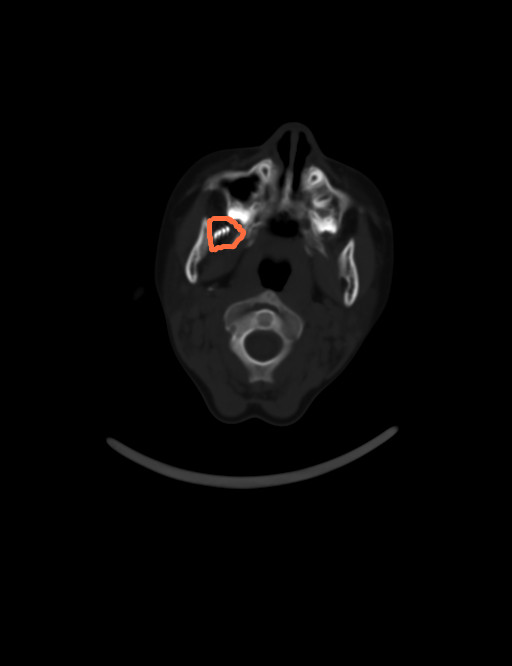

由于牙刷无法拔除,医院耳鼻咽喉头颈外科值班医师立即给辰辰进行了CT检查,结果显示右侧口腔--颞下窝可见条片状稍高及高密度影,右侧颞下窝局部软组织肿胀、层次不清,内可见气体样密度影,诊断为右侧口腔--颞下窝异物。医师连夜为辰辰实施了急诊手术,顺利取出约牙刷头。